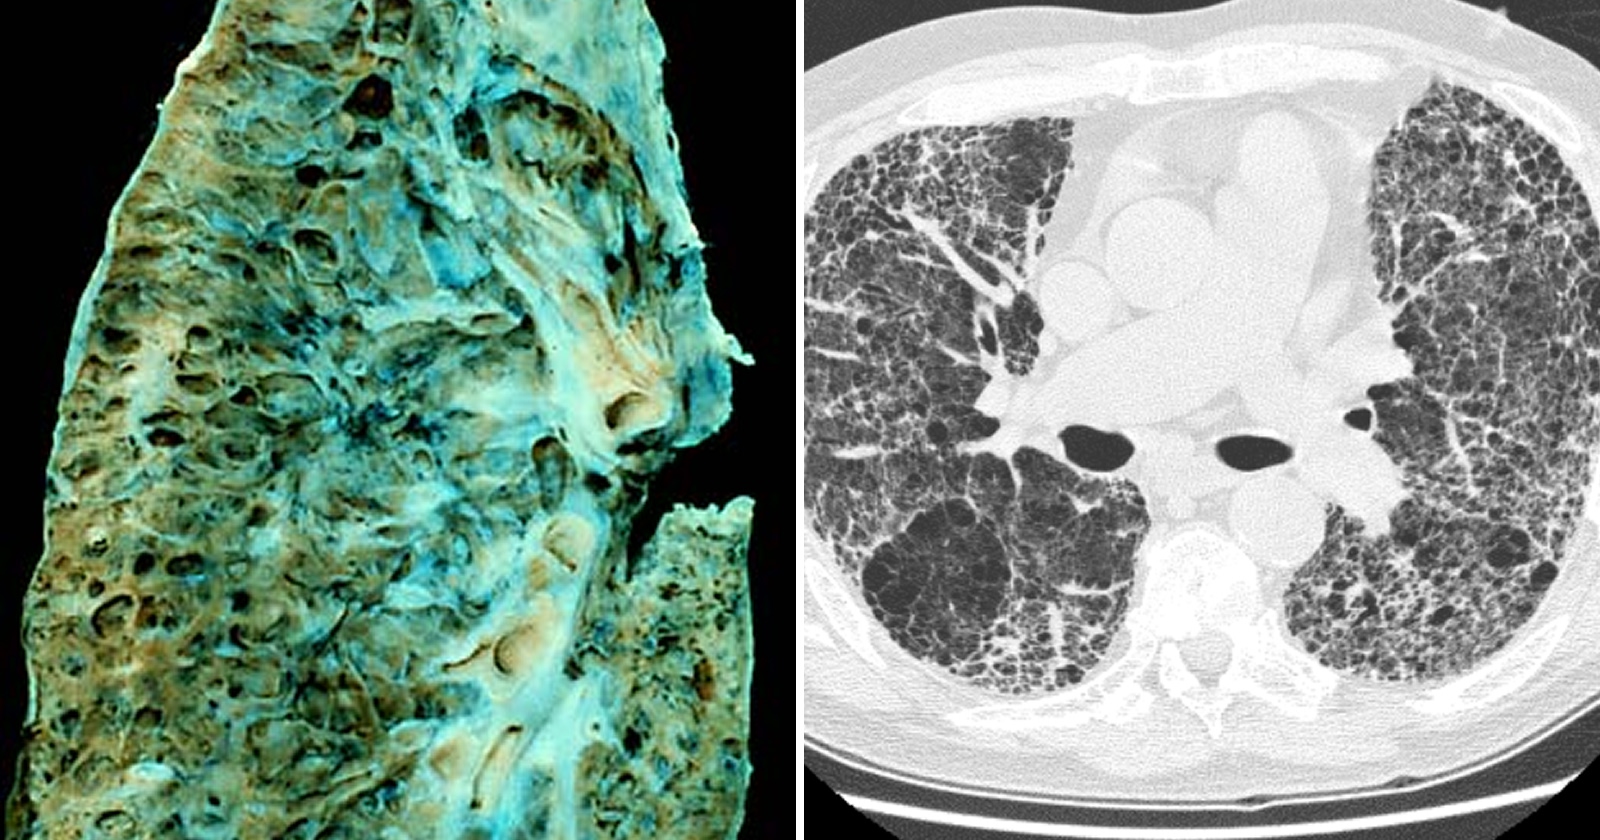

Vo vzduchu je smrť. Presne tak by mohli opísať svoje posledné chvíle stovky ľudí v Južnej Kórei na sklonku prvej dekády 21. storočia. Zúfalí rodičia privážali do nemocníc novorodencov s pľúcami, ktoré vyzerali, akoby ich deti strávili 30 rokov prácou v uhoľnej bani. A to napriek tomu, že za sebou mali len niekoľko týždňov života.

Medzitým tichý a neznámy nepriateľ kradol život aj tehotným ženám, menším deťom a dovtedy zdravým dospelým. Pacienti prichádzali do nemocníc s neznámym ochorením pľúc, ktoré sa v lekárskych príručkách nedalo dohľadať. Jeho priebeh však pripomínal akútnu intersticiálnu pneumóniu, známu pod skratkou AIP – chorobu, ktorá je prudká, agresívna a často končí smrťou.

K 31. augustu 2011 bolo hospitalizovaných už 28 dospelých pacientov, z toho 13 tehotných žien. Štyria pacienti medzitým zomreli na následky pľúcnej fibrózy (nezvratného poškodenia pľúc).